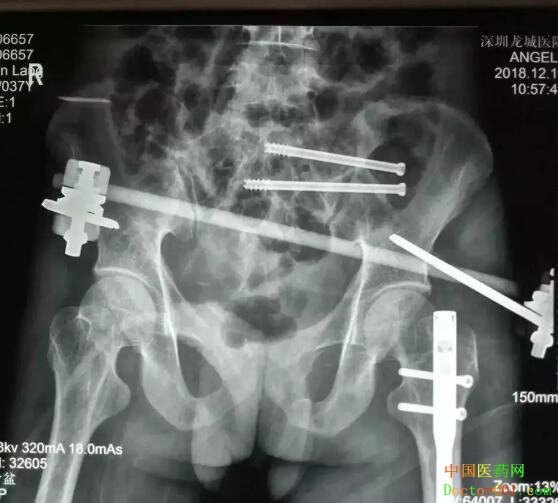

覃先生:“当时完全懵了,只感到下身剧烈疼痛,全身发冷,有一种死亡来临的感觉。” 覃先生回忆说,住进医院后自己翻身都不行,只是感觉到全身都痛,难以忍受。 由于覃先生病情非常危重,医院立即开启绿色通道,紧急安排住进骨科抢救室。根据检查结果初步诊断覃先生为重症多发伤。骨科博士汪金平详细介绍说,患者的主要诊断包括:① 创伤性休克;② 骨盆多发不稳定骨折:左侧骶骨粉碎性骨折、右侧耻骨上下支粉碎性骨折;③ 左侧股骨干骨折;④ 右侧踝关节骨折;⑤ 急性失血性贫血等情况。

“这是一个很棘手的病例。”主治医生介绍,虽然经过及时的专业救治和护理,覃先生的病情日趋稳定,但患者系非常严重的不稳定型骨盆骨折,合并这种骨折的患者,受伤时伤力都非常大,受伤部位也比较多,所以病情都比较复杂而严重。 由于骨盆骨折极度不稳定,断骨需要快速生长骨痂,所以骨盆骨折的最佳手术时机是伤后一周内,否则将无法闭合复位骨折及无法实施创伤最小的经皮内固定术,最终的治疗效果可能比较差,主治医生分析说。 由于患者情况比较复杂,主治医生申请全院多学科专家会诊,详细分析患者病情,进一步评估手术风险,专家组讨论认为,患者系全身多处骨折,并且损伤严重,合并严重的全身性炎症反应,争取全身骨折用一次手术就全部做好,但长时间的麻醉会影响手术后肺功能的恢复,因此,要将手术的损伤降低到最小,同时要在最短的时间内完成手术。 影像资料显示,患者骶1椎存在发育畸形,这种骶骨畸形增加了实施骶髂螺钉固定的风险,因为骶骨里和周围有大量的神经和血管呈网状分布,手术中一点偏差可能造成无法挽回的严重后果,轻者损伤神经造成患者瘸腿,重者损伤血管导致大出血而造成患者死亡。 经过慎密的研究,专家组认为患者身体条件不适合实施传统的切开复位固定术,实施微创固定术对患者是最佳治疗选择。

12月14日,在患者伤后第三天,由博士带领团队为患者施行了透视下实施经皮骶髂螺钉固定术,首先闭合复位骨盆骨折成功,即刻经皮置钉完成前环外固定架固定术以稳定骨盆。然后顺利地经骶1椎和骶2椎各置入一枚骶髂螺钉固定,至此骨盆的前后环均获得牢固固定。手术历时近2小时,所有切口加起来的总长度不超过5cm,手术中出血不到10毫升。术后复查显示骨折复位和内固定位置都很好,医生评估预计手术后三个月可以正常行走。 覃先生 : “手术完,几乎没有感觉到痛苦,术后当天,已经可以背靠在床上坐起来吃饭了。”“汪医生水平很高,人也很好。”